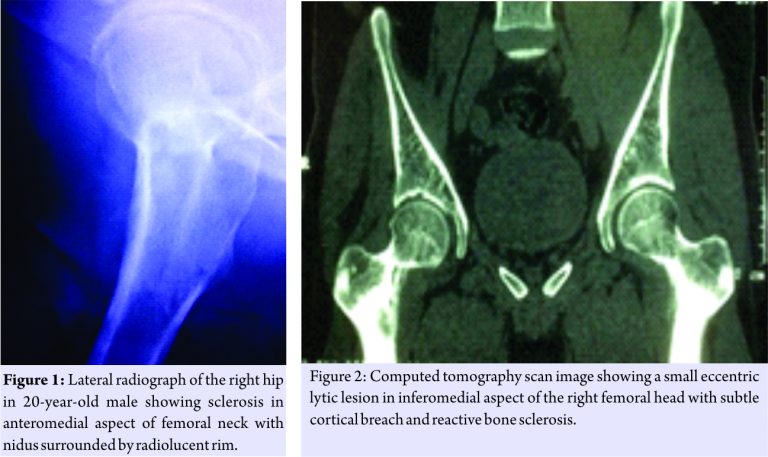

A 20-year-old male presented to us with pain in the right hip for 1 year with gradually developing limp over a period of 2 months. Initially, the pain was mild in intensity which gradually progressed to moderate intensity within a period of 1 year. Now, pain is continuous in nature, interfering with activities of daily living and relieved by taking pain medication. Since past 2 months, he noticed limp, which was progressive and associated with pain. He has been taking pain medication intermittently for past 1 year. He even took antitubercular treatment for 2 months which he stopped on its own. Previous magnetic resonance imaging scan reported synovial effusion with altered signal intensity at anteroinferior aspect of the right femoral head. He was diagnosed with monoarticular juvenile rheumatoid arthritis and referred to our center. Physical examination revealed tenderness in anterior aspect of hip joint. Movements were terminally restricted due to pain. Blood count and biochemical profile are within normal range. Careful evaluation of radiographs showed sclerosis in anteromedial aspect of femoral neck with nidus surrounded by radiolucent rim suggestive of osteoid osteoma (Fig. 1).Computed tomography (CT) scan clearly shows a small eccentric lytic lesion in inferomedial aspect of the right femoral head with subtle cortical breach and reactive bone sclerosis (Fig. 2).